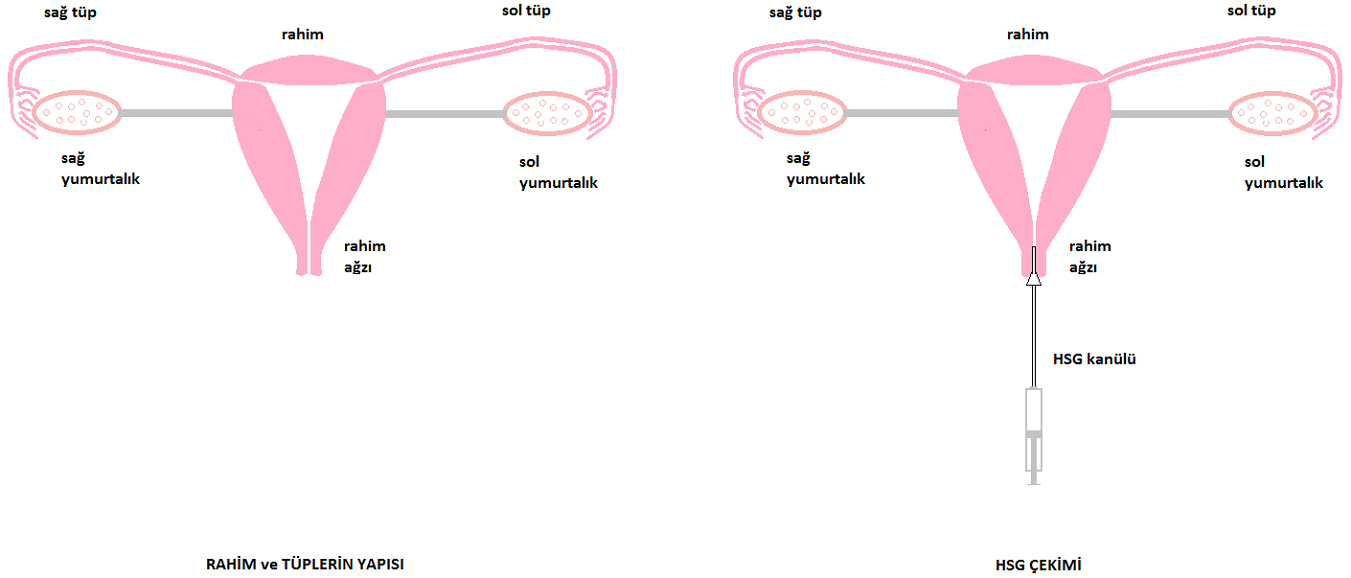

يظهر الشكل التشريحي الطبيعي للرحم والأنابيب في الشكل.

يوضح الشكل البنية التشريحية الطبيعية للرحم وقناتي فالوب.